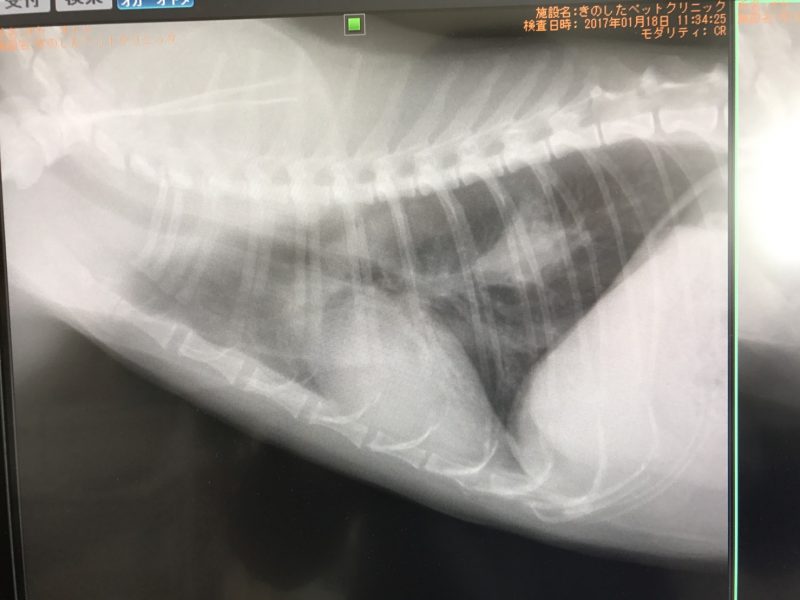

レントゲンの画像でいつもじわじわと広がっていく忌々しい影を見て、猫の乳がんとおっちゃんの悪性度を理解しているけど

そして、画像です。

でも、これはすごい!!まじで??うそ!!は?これが今日?あ?みたいな

先生も稀に見ることだ・・・と。

腫瘍の大きさが前回の半分になっていたんです。

そして、最初に撮った時の大きさと変わらない、もしくは若干小さくなっている・・・。

誰が見ても分かる

↓水曜日

すごいやろ!倍率明るさはほぼ同じだよ!明るさの違いははカメラだから

↓ 左が最初、右が水曜日

大きさが変わらない、測ると若干小さいの。

現状維持ができればおっちゃんの肺の状態では十分、小さくなれば万々歳だった。